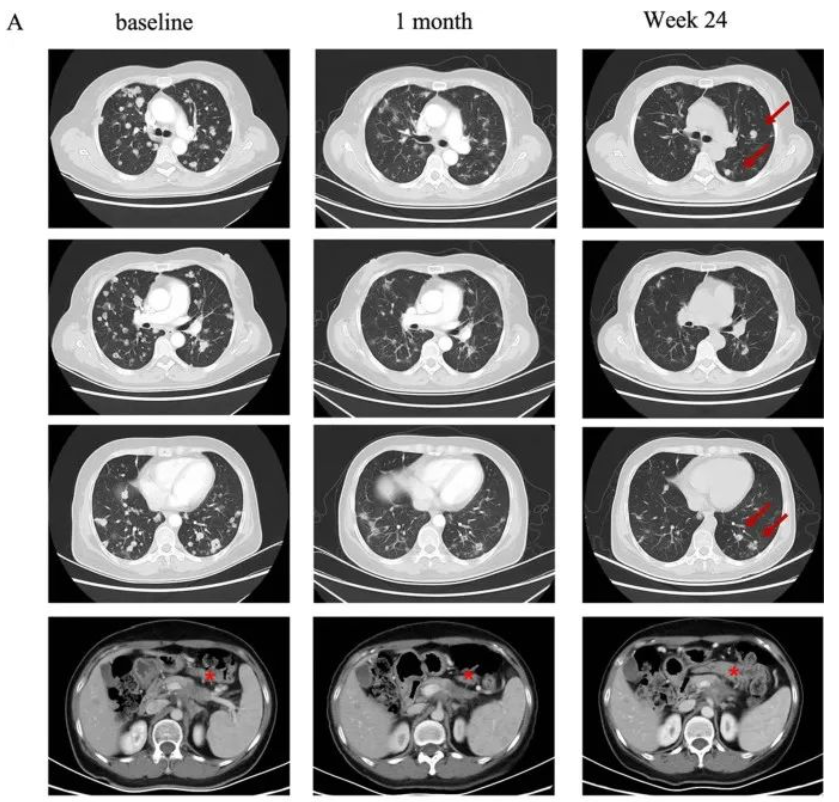

典型病例1

一名58岁的女性胰腺癌患者,伴有肺及淋巴结转移。该患者先后经历一线白蛋白紫杉醇联合吉西他滨和二线伊立替康联合5-氟脲嘧啶治疗后失败。经检测其Claudin18.2表达为2+/70%后入组CT041临床试验。

在进行氟达拉滨、环磷酰胺、白蛋白紫杉醇方案清淋预处理后,患者于2021年9月接受CT041细胞输注。输注后患者出现2级细胞因子释放综合征(CRS),在接受托珠单抗后恢复。根据RECIST v1.1标准,患者肿瘤评估达到部分缓解(PR),肺部转移灶明显缩小。